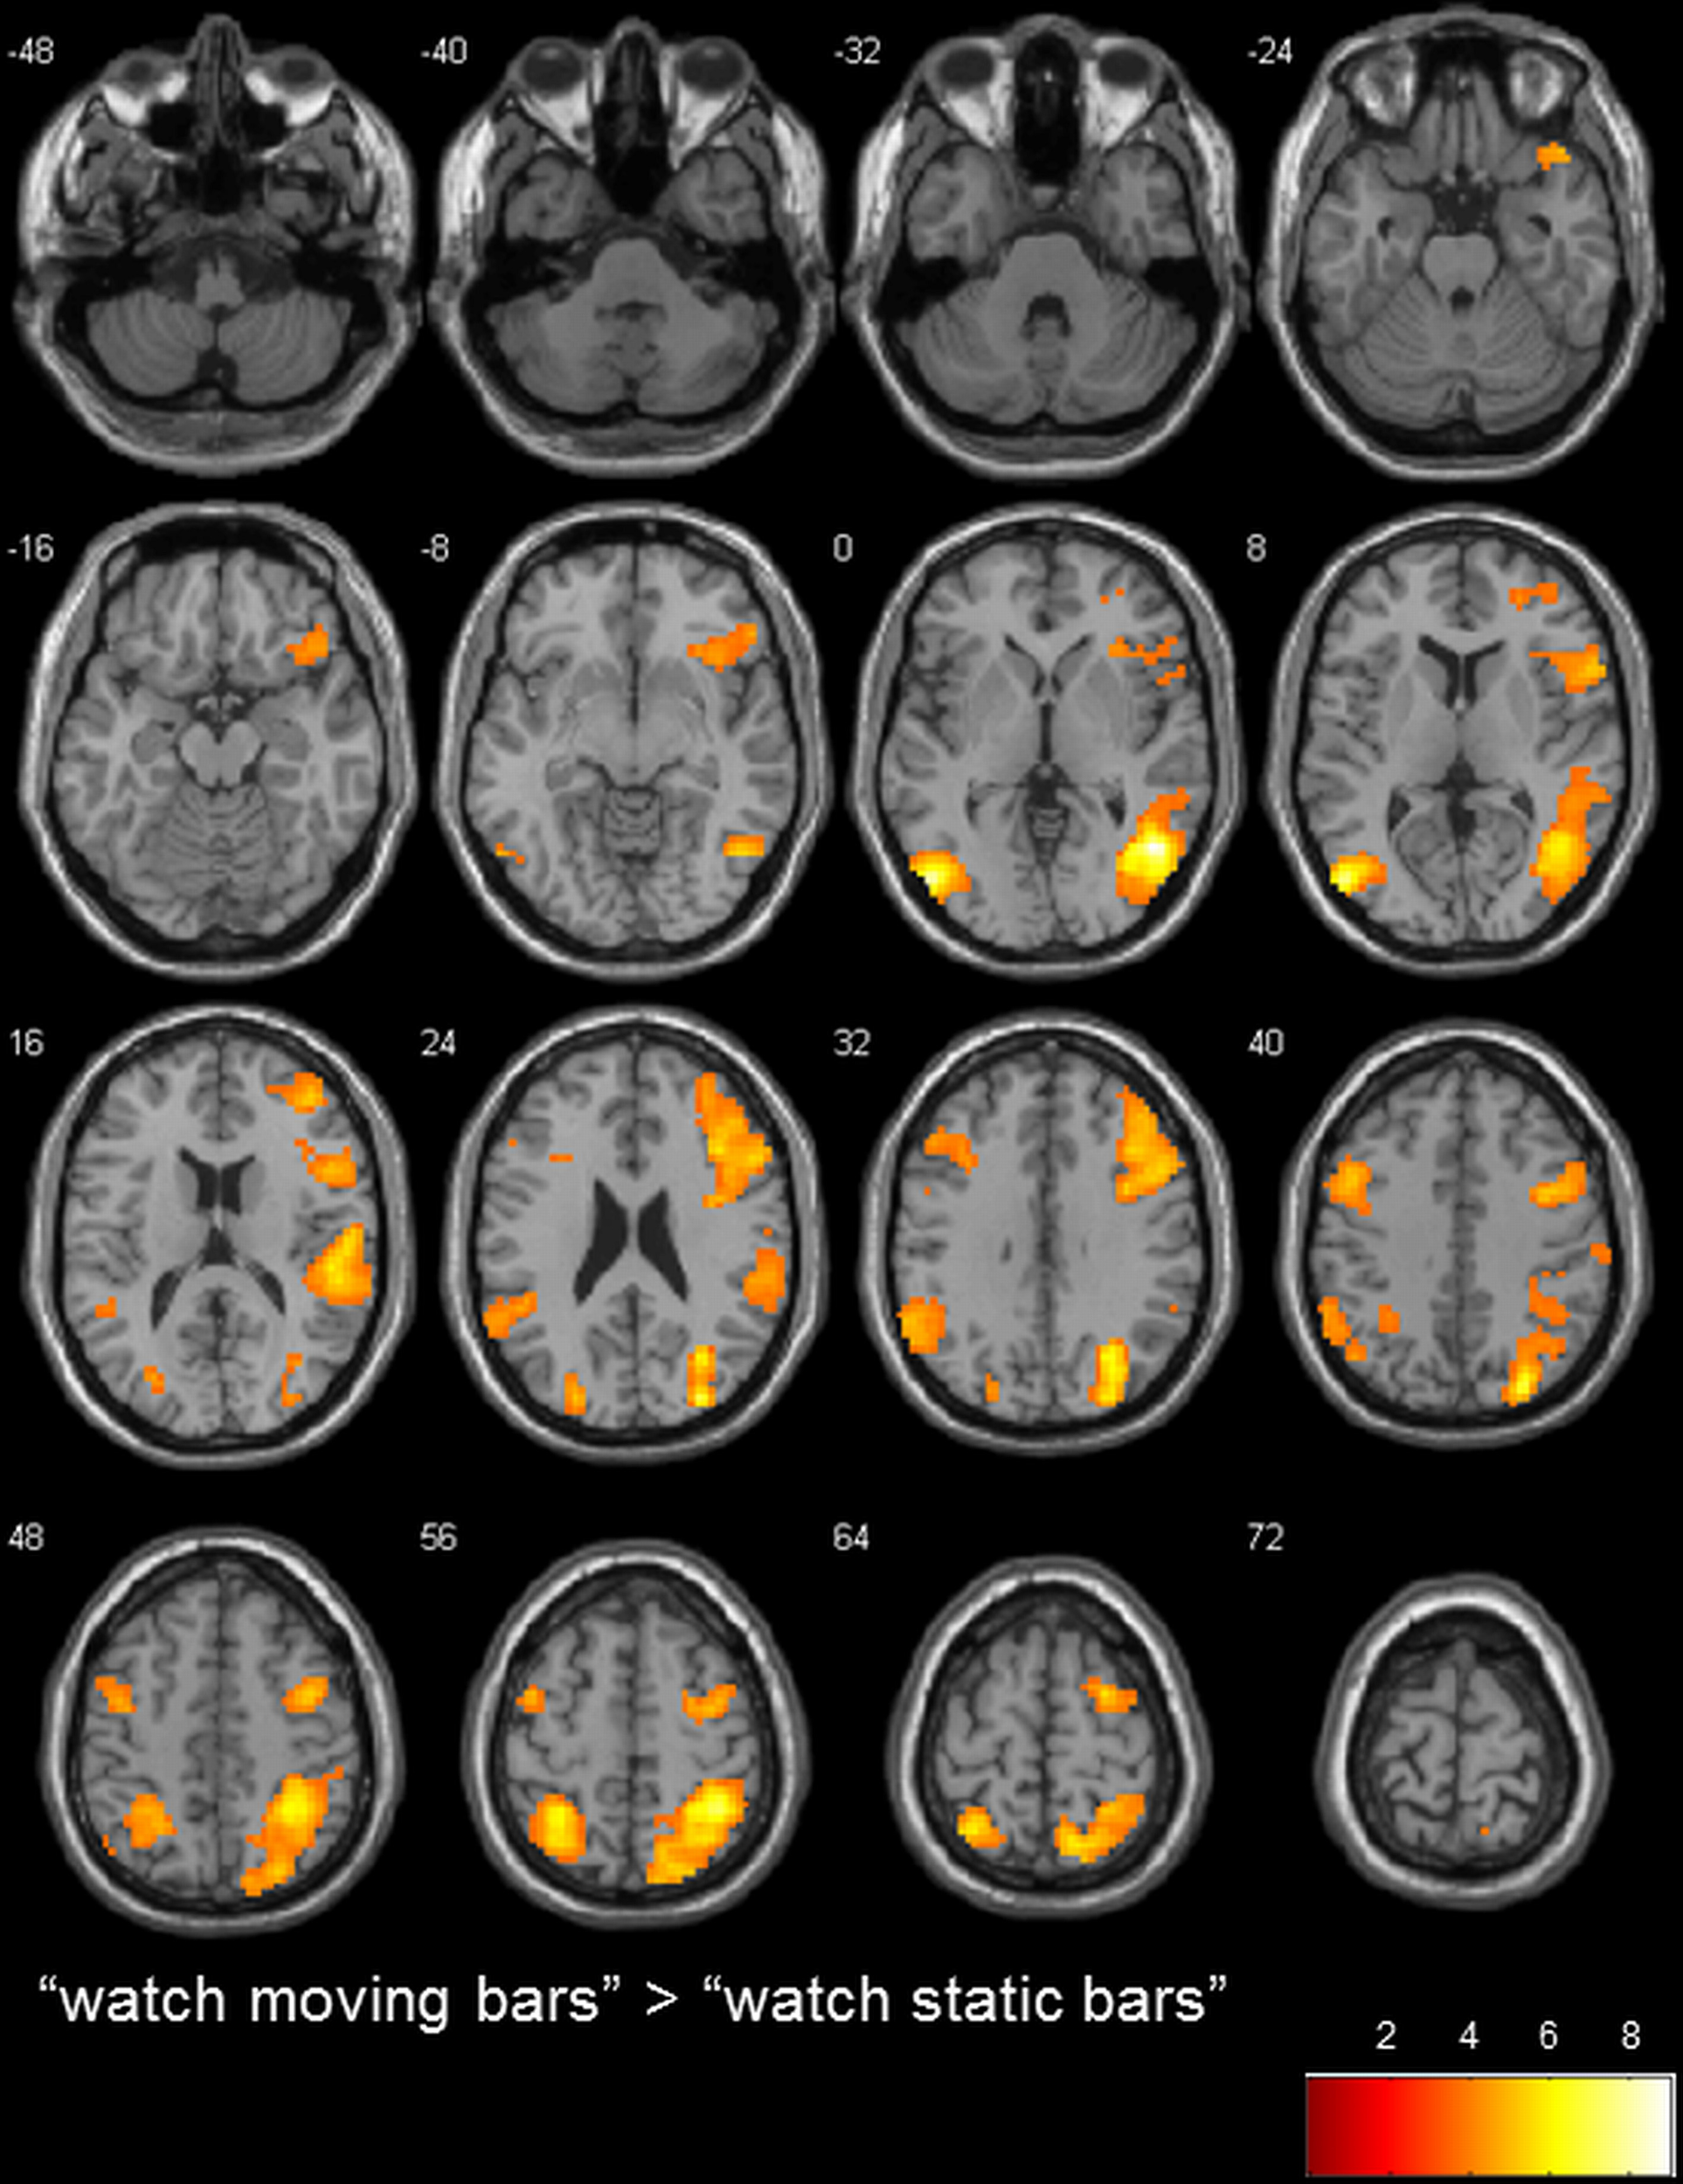

To determine the general level of activation when participants observed a moving bar, we used the contrasts of “watch moving bars” > “watch static bars” and “watch static bars” > “watch moving bars.” A broad network of activation covering the right and left temporo-parietal and inferior frontal areas was observed after subtracting the activity of “watch static bar” from “watch moving bars” (Table 3, Figure 3).

FIGURE 3

www.frontiersin.org

Figure 3. transversal slices (8 mm spacing); t-score map for “watch moving bars” > “watch static bars”; p < 0.001 uncorrected on voxel-level, p < 0.05 corrected for multiple comparisons on cluster-level (false discovery rate [FDR]); minimum cluster size 10 voxels.

To our knowledge, this is the first study which examines the neural correlates of executive control in a NF-like paradigm using fMRI. In comparison to the control condition “watch static bars,” stronger activation in a broad network of regions distributed over the right temporal cortex, inferior and superior parietal cortex, fusiform gyrus, posterior insula, left middle occipital gyrus, left superior parietal lobule, right inferior frontal gyrus, left supramarginal gyrus and left precentral gyrus was observed in the condition “watch moving bars.” The activations observed in occipital, temporal and parietal cortex reflect probably the processing of bar movements (Burr and Morrone, 2012), while the activations observed in the inferior frontal gyrus, bilaterally, reflect probably an increase of attention to inner states (Craig, 2009), since in this condition participants were told that they were seeing their own brain activity represented by the moving bar.